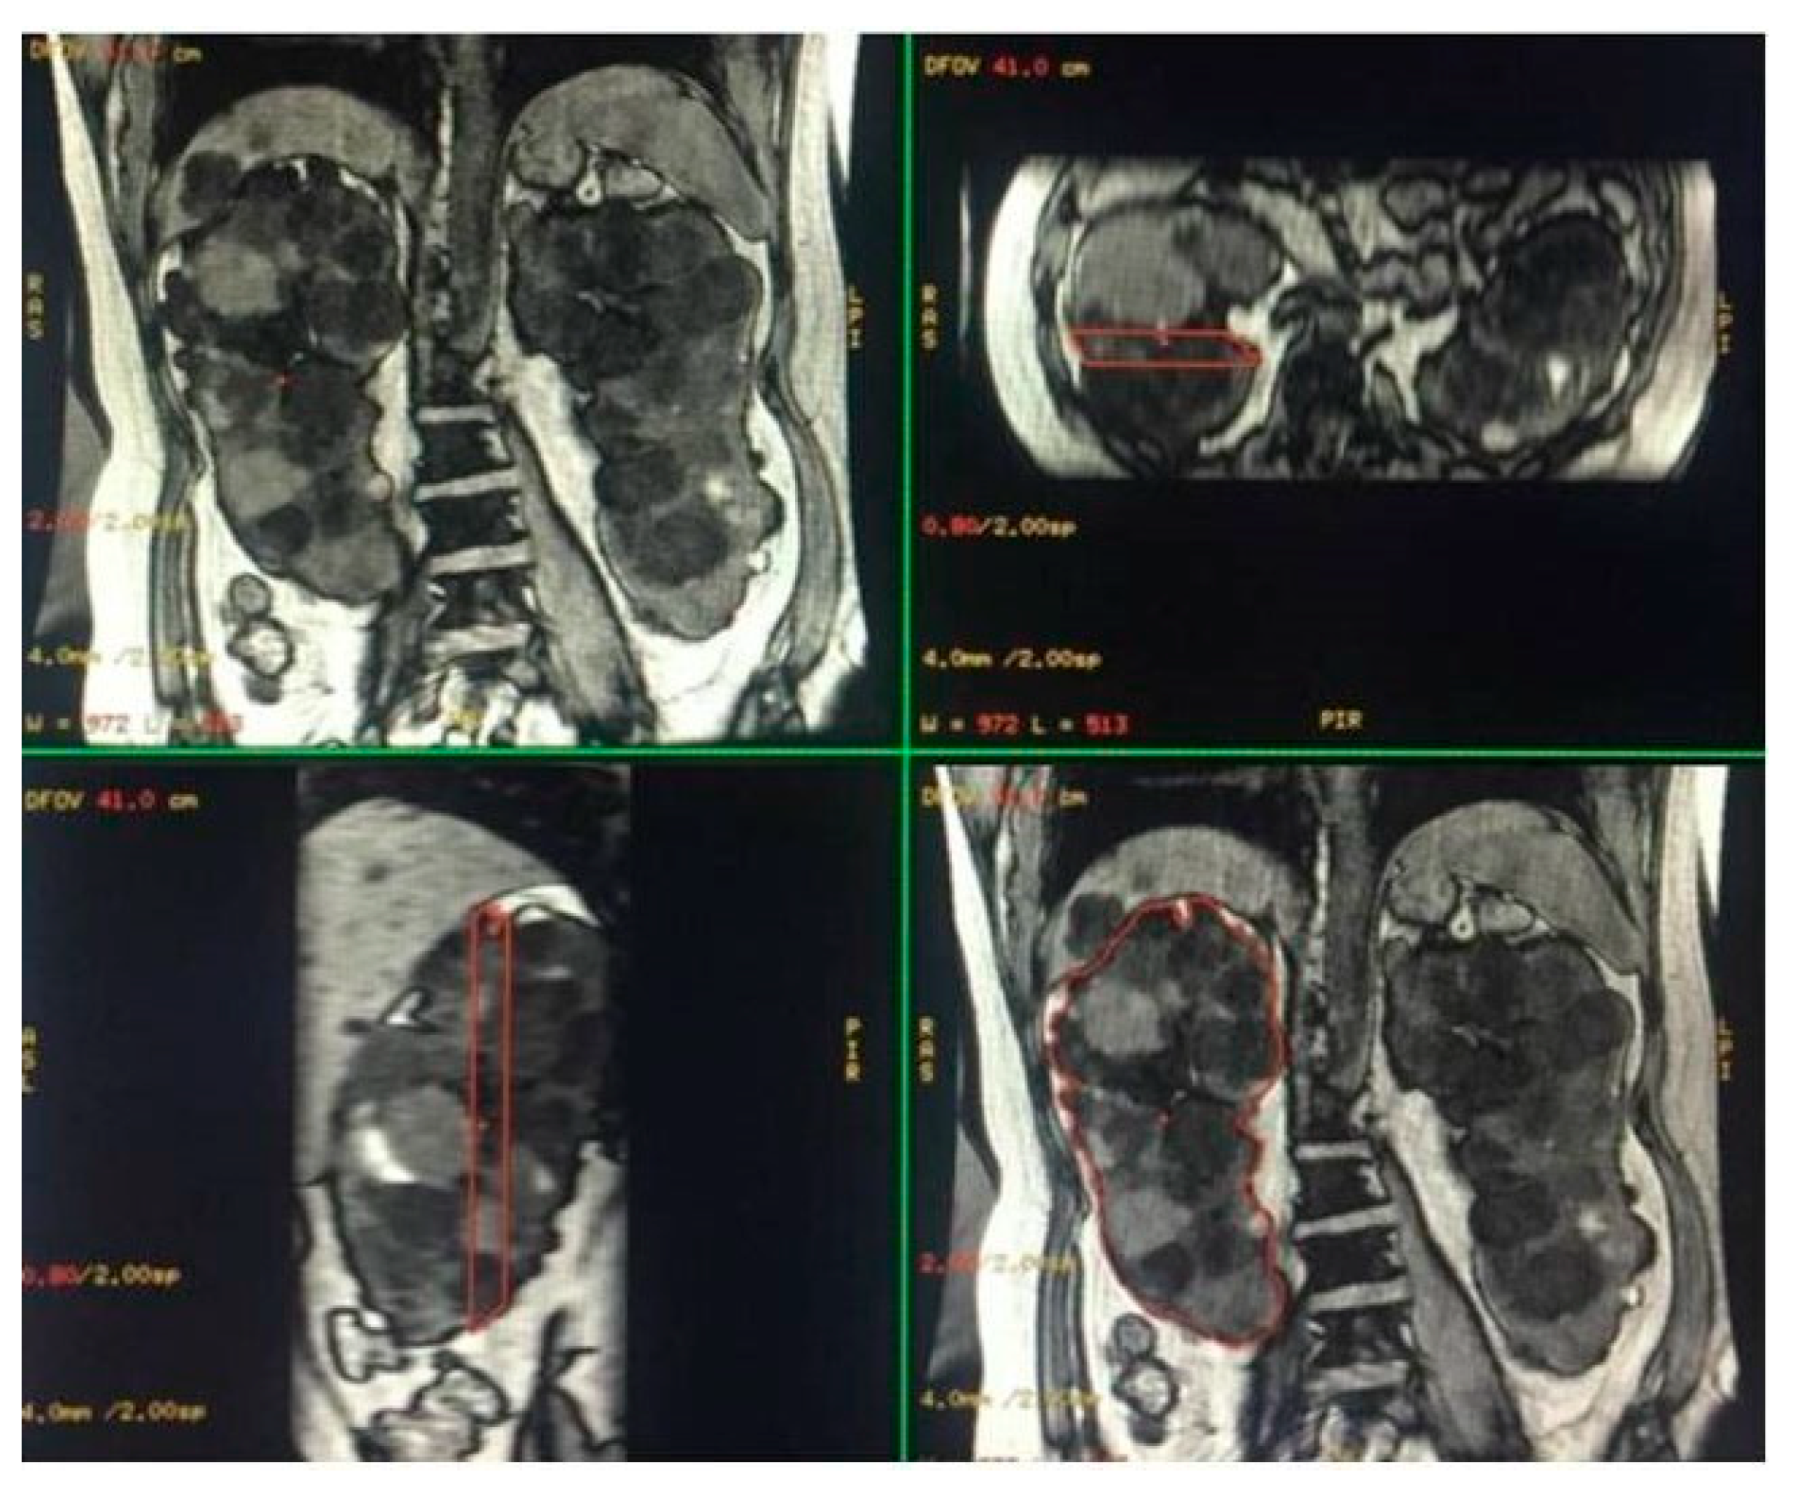

Figure 2.

Semi-automatic volumetric segmentation. View of images in the three planes of space during segmentation.

Figure 3.

Representative images of the semi-automatic volumetric segmentation method performed on two different patients. This method requires manual tracing of renal contours on some images—Coronal 3D Dual Echo (A) or axial LAVA (B)—with automatic reconstruction in the intermediate images. Extraction of the segmented kidney volume with SKV computation on the same contour plane (C,D) and reconstruction in volume rendering (E,F).

For this type of segmentation, the 3D sequences were selected; Coronal 3D T1 Dual Echo acquisitions were preferred for the shorter time requirement for semi-automatic segmentation; however, sometimes, due to the presence of motion artifacts or for greater operator confidence, the axial LAVA sequences were used. Both operators used the same sequence on the same patient to perform the semi-automatic volumetric segmentation.